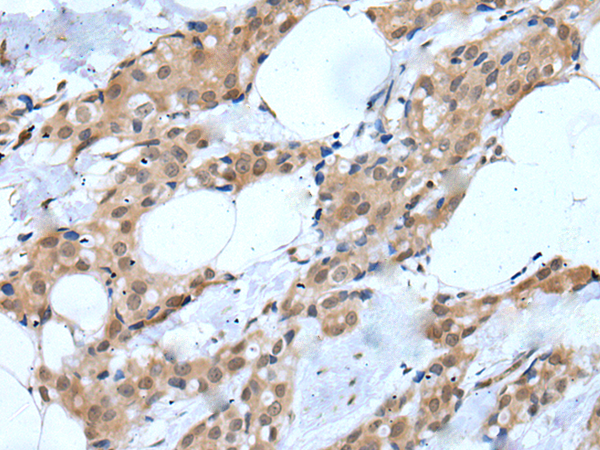

IHC positive control: |

Human esophagus cancer and human breast cancer |

IHC Recommend dilution: |

25-100 |